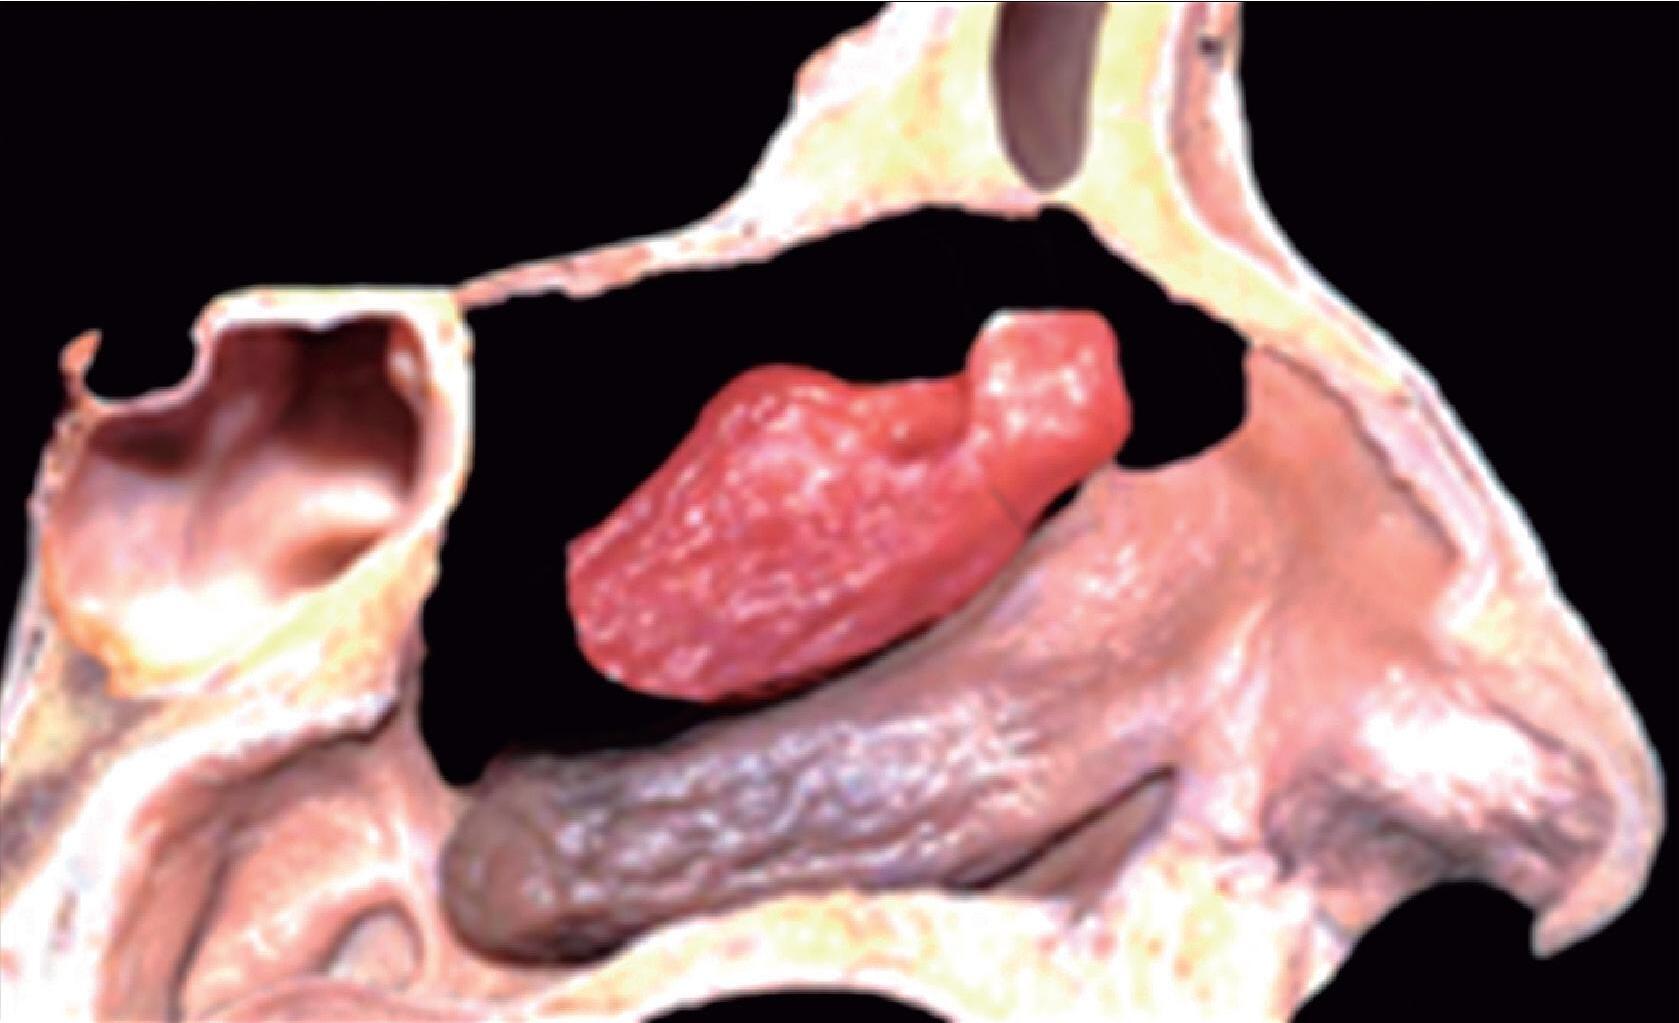

1-4. TC e reconstrução 3D com destaque para estrutura etmoidal (em vermelho), funcionando como câmaras de baixa pressão para drenagem do seio maxilar.

1-7. TC com reconstrução 3D mostrando em vermelho apenas o seio etmoidal e não o osso etmoidal, e sua relação com a fossa nasal, o seio maxilar, órbita e fossa anterior.

Este complexo anatômico chamado seio etmoidal, controla a pressão e o fluxo aéreo que penetra nos verdadeiros seios paranasais e pode ser interpretado como um sistema de câmaras aerodinâmicas de baixa pressão cuja topografia particular faz dele o centro anatomofuncional do aparelho rinossinusal.